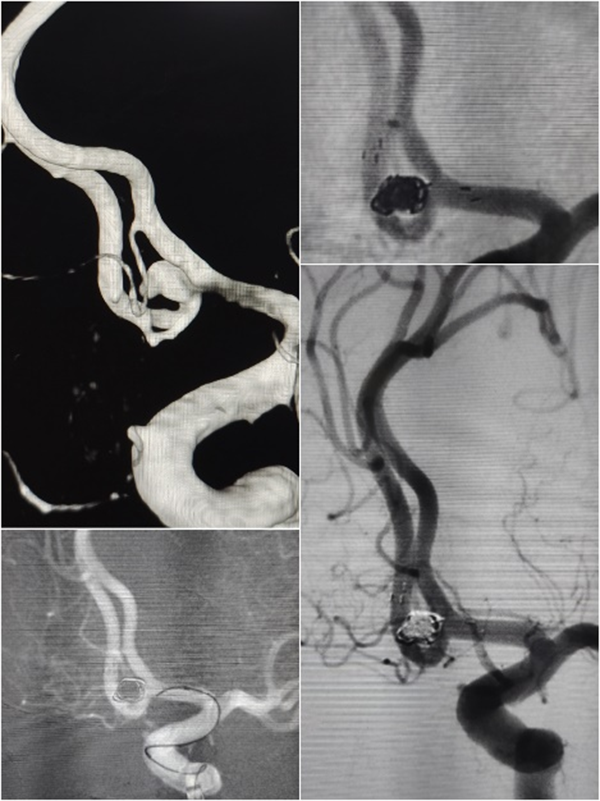

随着时间的推移,一例例复杂的全麻手术被成功完成:

青年卒中患者

全麻下椎动脉颅内段亚急性期闭塞再通术

基底动脉夹层管腔线样狭窄

全麻下支架植入术

全麻下大脑中动脉亚急性期闭塞再通术

高龄患者左颈内动脉C7段重度狭窄

全麻下支架术

高龄患者前交通不规则动脉瘤

全麻下支架辅助弹簧圈栓塞术

高龄老人椎动脉长段次全闭塞

全麻下多支架再通术

让我印象深刻的是位39岁的年轻男性患者,突发头晕伴右侧肢体麻木无力、言语不利,脑血管造影显示:椎动脉颅内段血管闭塞。患者病情复杂,血管闭塞节段长,而且血管条件差,开通闭塞血管的手术风险也相应增加,但如果选择保守治疗,将来发生严重卒中的风险非常高。

张主任带领团队对患者病情进行了细致分析,制定了详细的手术方案及预案,手术仅耗时40余分钟,夜里23:40,手术圆满结束。